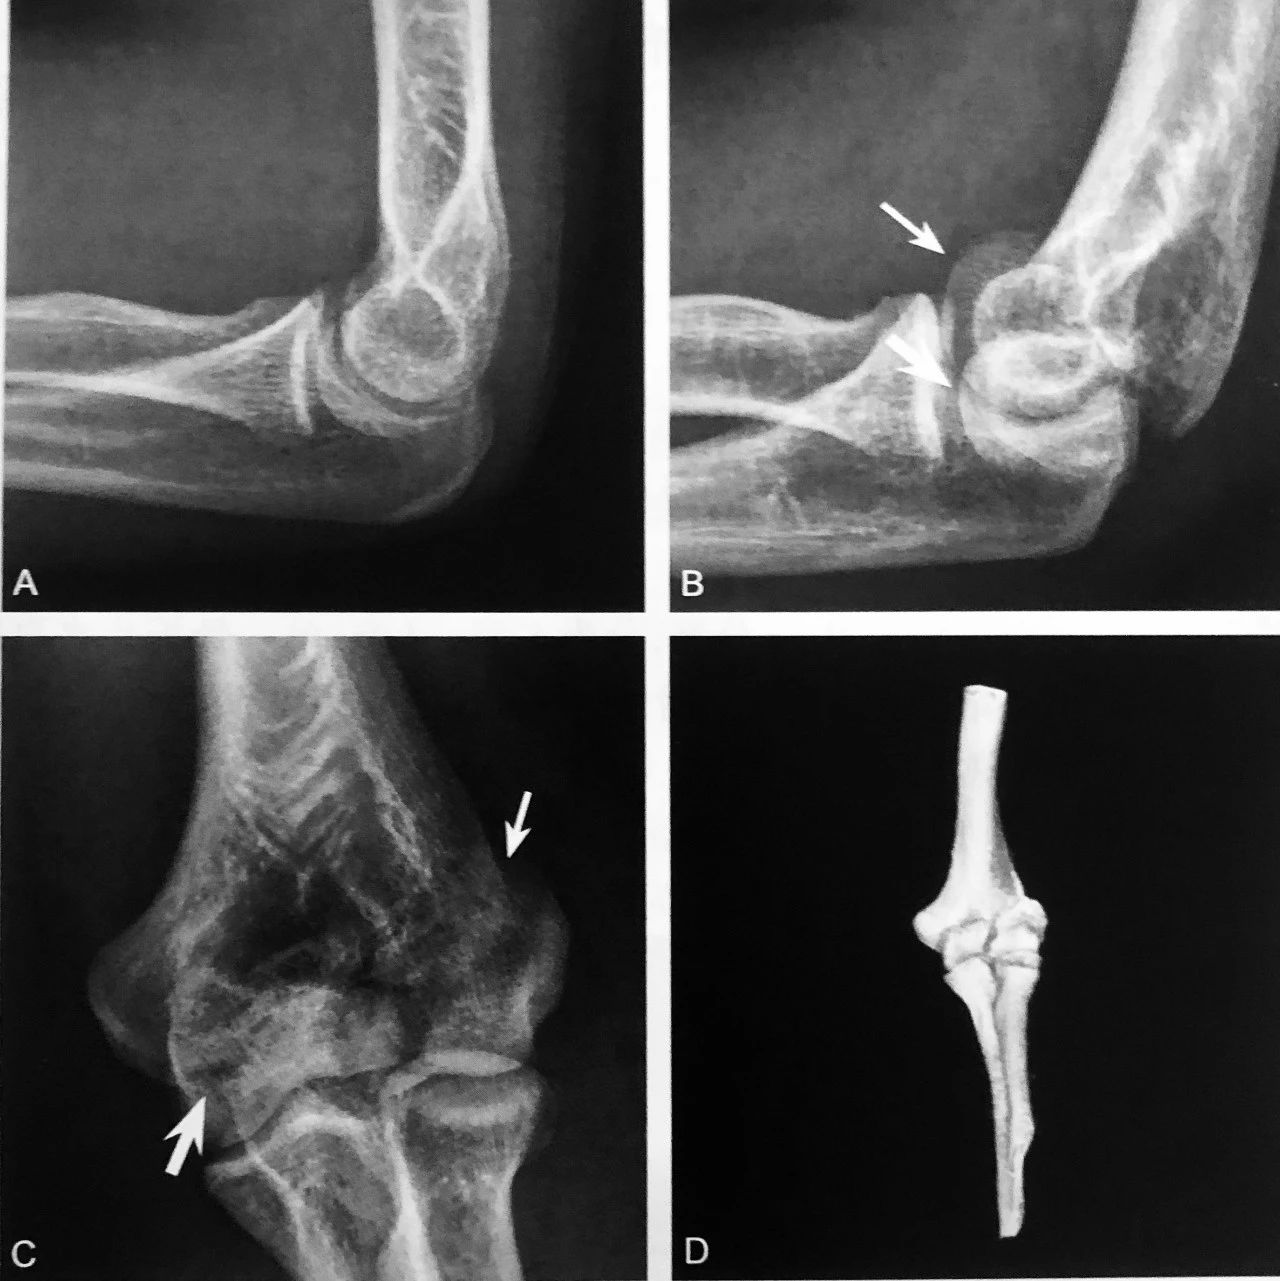

双肩锁关节征:A 图冠状位压脂 PD 序列显示,肩峰关节面下可见游离的条状、未融合肩缝小骨(箭头),肩锁关节囊积液,伴肩峰下-三角肌下滑囊积液,同时可见冈上肌肌腱撕裂(三角);B 图矢状位压脂 PD 序列显示:未融合肩峰小骨与肩峰关节面、肩锁关节形成双肩锁关节,肩锁关节囊积液,伴肩峰下-三角肌下滑囊积液(箭头)

判读要点:

1、在肩关节 MRI 冠状位或矢状位观察;

2、须同一层面同时观察到肩锁关节及肩峰小骨;

3、注意双肩峰关节征与第二肩锁关节区别;

4、观察肩峰小骨是否稳定,如不稳定,是否与邻近软组织产生撞击,此时应注意观察是否伴有周围积液、水肿、肩锁关节损伤及肩袖损伤。